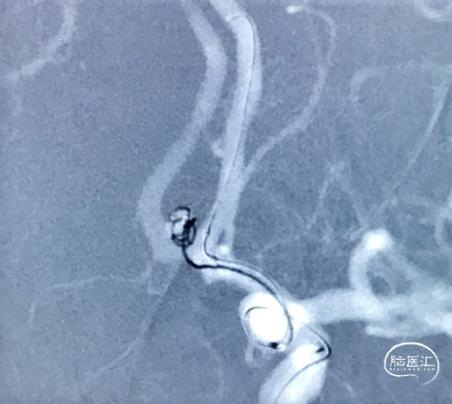

首先,选用Axium™ QC-3-6-3D弹簧圈进行成篮

第一枚弹簧圈成篮

成篮后,将第一枚弹簧圈解脱,然后充盈球囊,让弹簧圈更好的进入瘤腔内,之后在球囊辅助下,分别填入Axium™ QC-3-4-3D、2-6、Axium™ QC-2-3-HELIX 弹簧圈各一枚进行填塞,最后填入两枚Axium™ QC-1.5-2-HELIX 弹簧圈进行收尾

球囊辅助下栓塞

填入第二枚弹簧圈